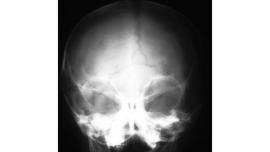

AI apocalypse: Will AI replace radiologists?

Artificial Intelligence, in its simplicity, includes processes that replicate human intelligence manufactured to provide effective solutions to problems. The exponential growth of artificial intelligence has a widespread reach in many sectors,

New robotic drill performs skull surgery 50 times faster

Researchers from the University of Utah create an automated machine that can do a complicated cranial surgery 50 times faster than standard procedures.